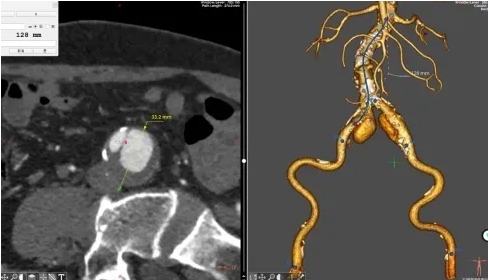

杨伯的CT显示:双侧髂总动脉瘤直径已分别达33.2mm(右)、23mm(左),超过3cm危险阈值,且伴有夹层形成可能,必须立刻手术。

2. 精准“排雷”:通过血管造影锁定腹主动脉瘤(伴血栓)、双侧髂动脉瘤位置;